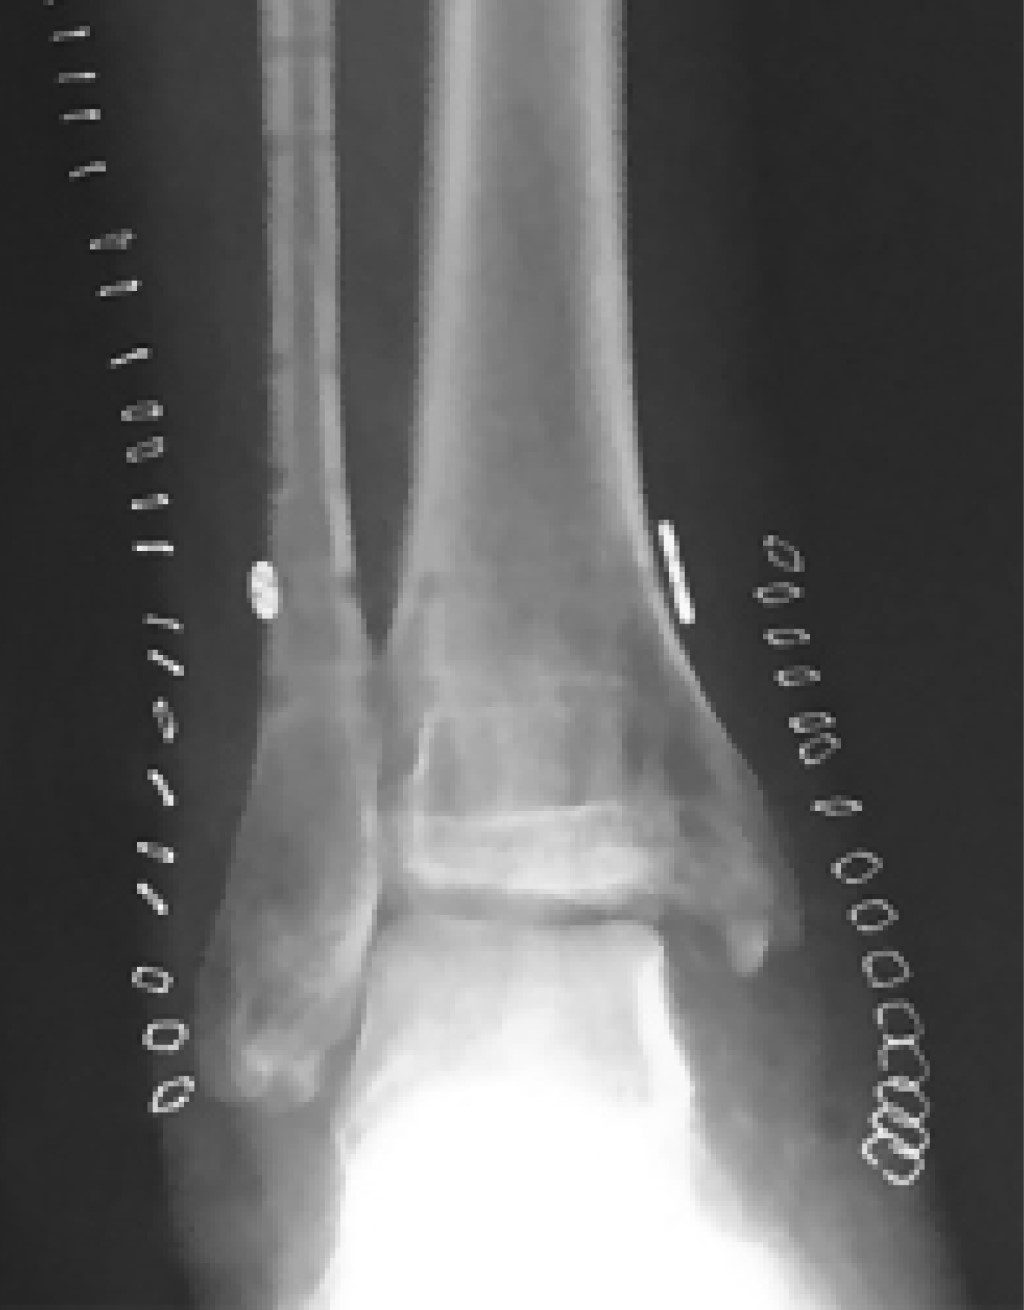

The CT Scan confirmed a medial malleolus rotational malunion with a bone fragment that blocked the ankle dorsiflexion. There was also a talar lateral translation causing tibiotalar incongruency and syndesmosis malreduction, with diastasis (Figure 3).

The ankle AP radiograph (Figure 9) showed joint incongruency with valgus malunion of the medial malleolus, talus lateral translation, syndesmotic diastasis, and fibular shortening. Due to the unacceptable multiple site malunion, with severe clinical impact, we decided for revision surgery.